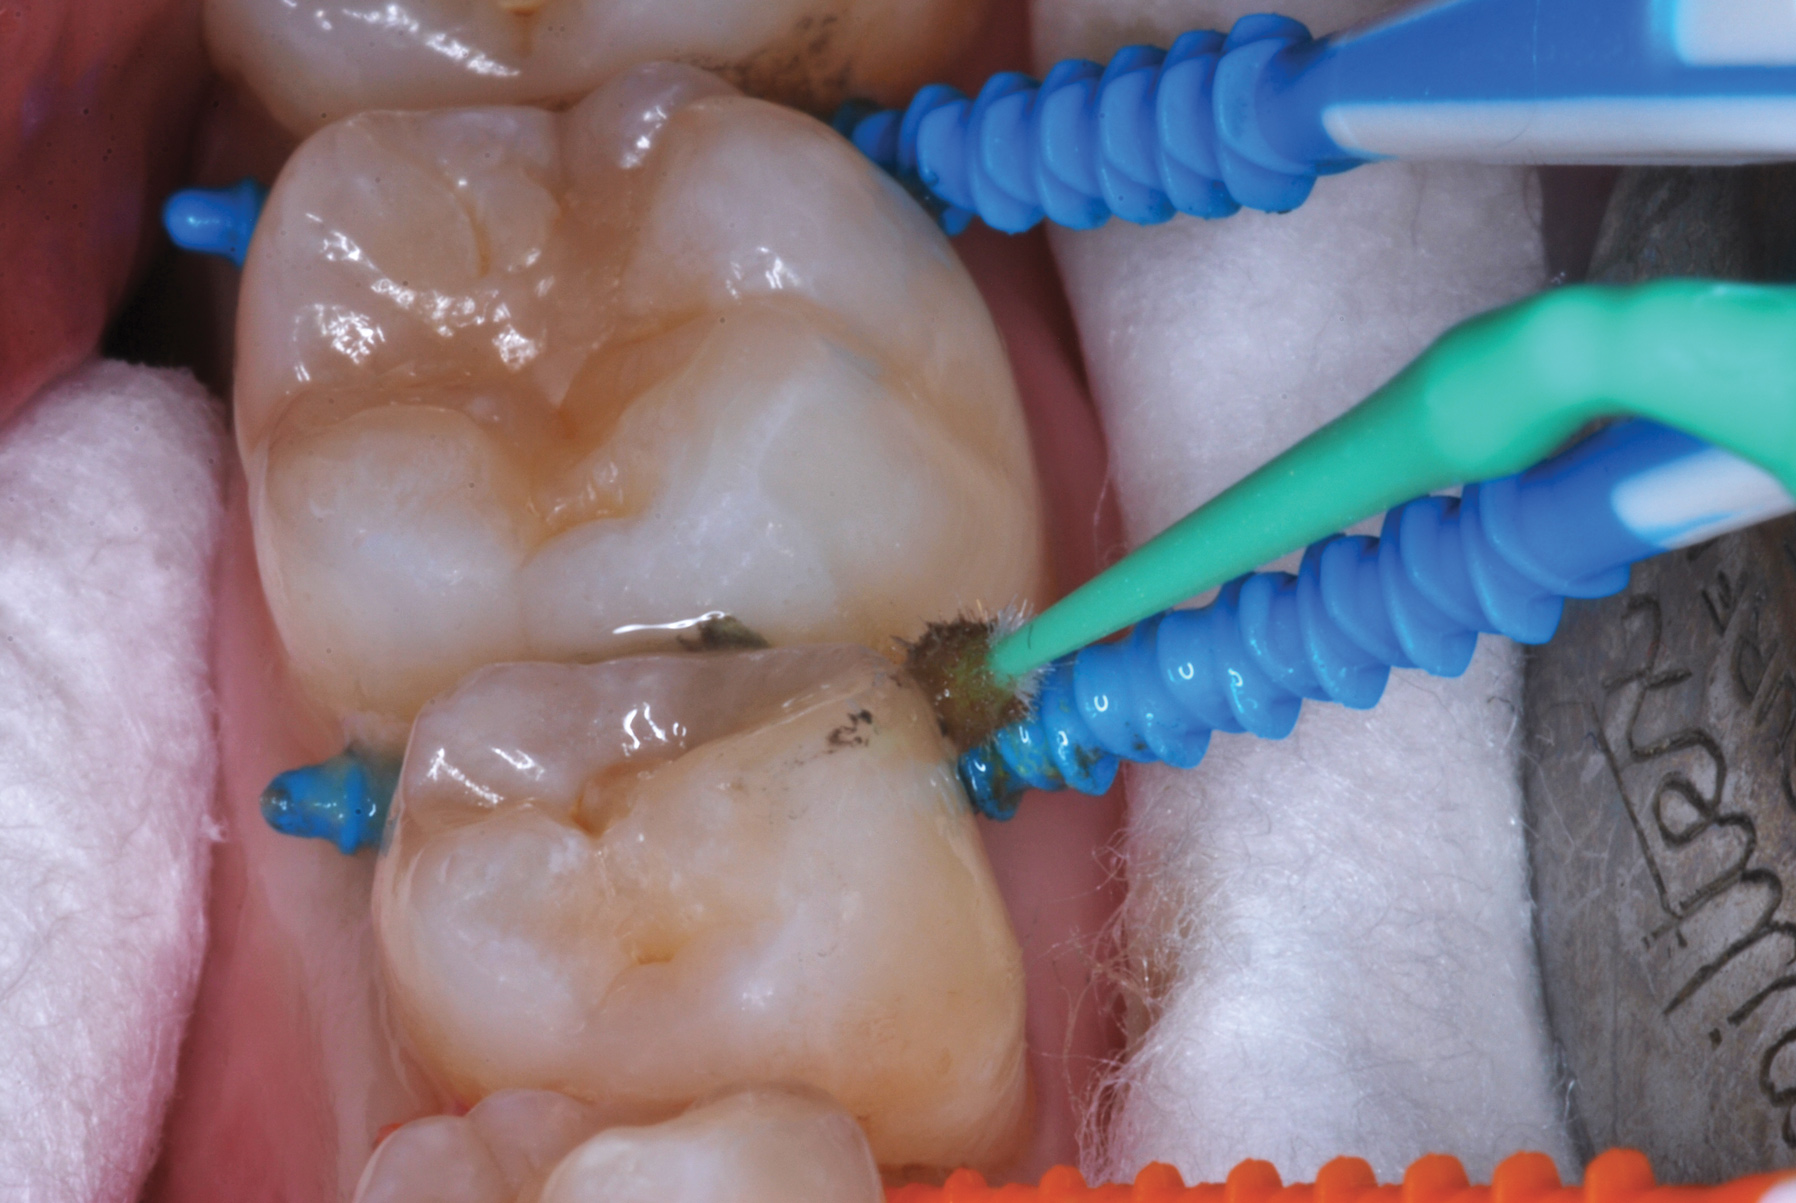

The authors' protocol for insertion of SDF-coated soft dental picks involves isolating the teeth with cotton rolls or other means, flossing the interproximal site to clear food debris and dental plaque, and then inserting a SDF-coated pick (Figure 1 and Figure 2) to saturate the contacting surfaces of the teeth with the fluid. This treatment is painless and requires no anesthetic. The pick should remain in place for at least 60 seconds and can be gently pulled in and out to agitate the fluid for enhanced surface coverage by capillary action. Additional SDF can be wiped on, using a small applicator, above the contact and in the buccal and lingual sluiceways. Excess fluid and any blood elicited may be blotted with a cotton swab. An additional 60-second insertion may be applied in the same way if there is radiographic evidence of a deeper decalcification or caries lesion. With the pick still in place, 5% (or 2.5%) fluoride varnish is painted over the treatment area, and the pick is then withdrawn.

Fig 3. Three thin soft dental picks were used simultaneously for SDF proximal surface saturations in a teenaged patient (Fig 3). After 60 seconds, the treated regions were covered with 5% fluoride varnish (Fig 4). A comparison can be seen of pre-SDF-treatment bitewing films (Fig 5) and 8-month post-SDF bitewing films (Fig 6) for the patient shown in Fig 3 and Fig 4. Radiolucencies were similar or improved, except for contact of maxillary first and second molars.

Figure 3